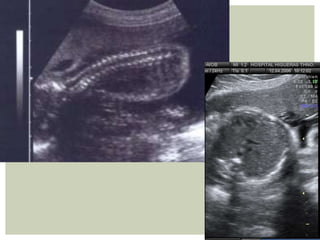

 Saco vitelino+ Embrión adyacente  Embrión inicialmente es líneal, luego en forma de “C”  Doppler mayor concentración de vasos en el sitio de localización placentaria  Se diferencia cavidad amniótica de coriónica  Se distingue polo cefálico de tronco (LCN 12mm)  Comienza a identificarse el amnios envolviendo completamente al embrión  Aparecen los esbozos de EESS  Embrión comienza a plegarse sobre sí mismo  Imagen de vesícula sonolucente, romboencéfalo, en polo cefálico  Se identifica cordón umbilical

• 22.

Aparecen esbozos deEEII Aparecen nuevas vesiculaciones en polo cefálico Comienzan los movimientos embrionarios Cavidad amniótica ocupa 50% de cavidad coriónica Se visualiza claramente cordón umbilical y su inserción Parte del intestino protruye en la base del cordón umbilical (Hernia umbilical fisiológica) Se comienzan a ver los plexos coroideos